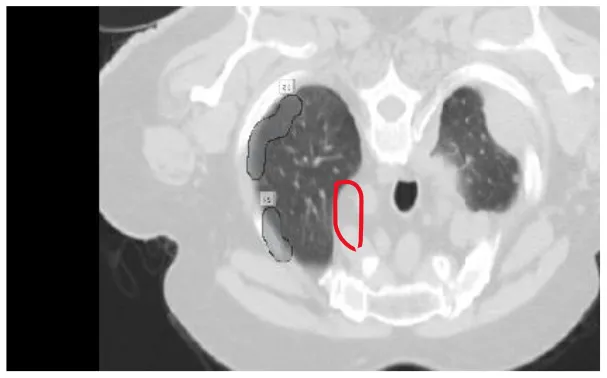

The results were enhanced by using the ROI segmentation method. It seems that it has the capacity to address the problem of the model's inaccurate positioning of labels. As a consequence, following the recommended methodology may lead to decreased losses. Furthermore, it was shown that the training session continued to slow down. The lesson is enhanced in its effectiveness as shown in Figure 8. It is advisable to apply the same treatment to both one-dimensional and two-dimensional data. The objective of this strategy is to eliminate any errors in labeling in both directions. Over time, there was a gradual reduction in the size of each point. Engaging in conversations with individuals helps achieve both objectives.

Figure 8

Prior to and during the segmentation procedure, the ground-truth forecast was used in each of these instances.

If the dataset is insufficient, it may be necessary to round up more labels. Overall, there were 159 cancerous tumors, and the standard deviation of the Dice coefficient was 0.2. Although its model had a low mFPI, the DL-based model was successful in detecting lung tumors from chest X-rays, the results are shown in Figure 8. The evaluations of the proposed models are presented in Table 8.